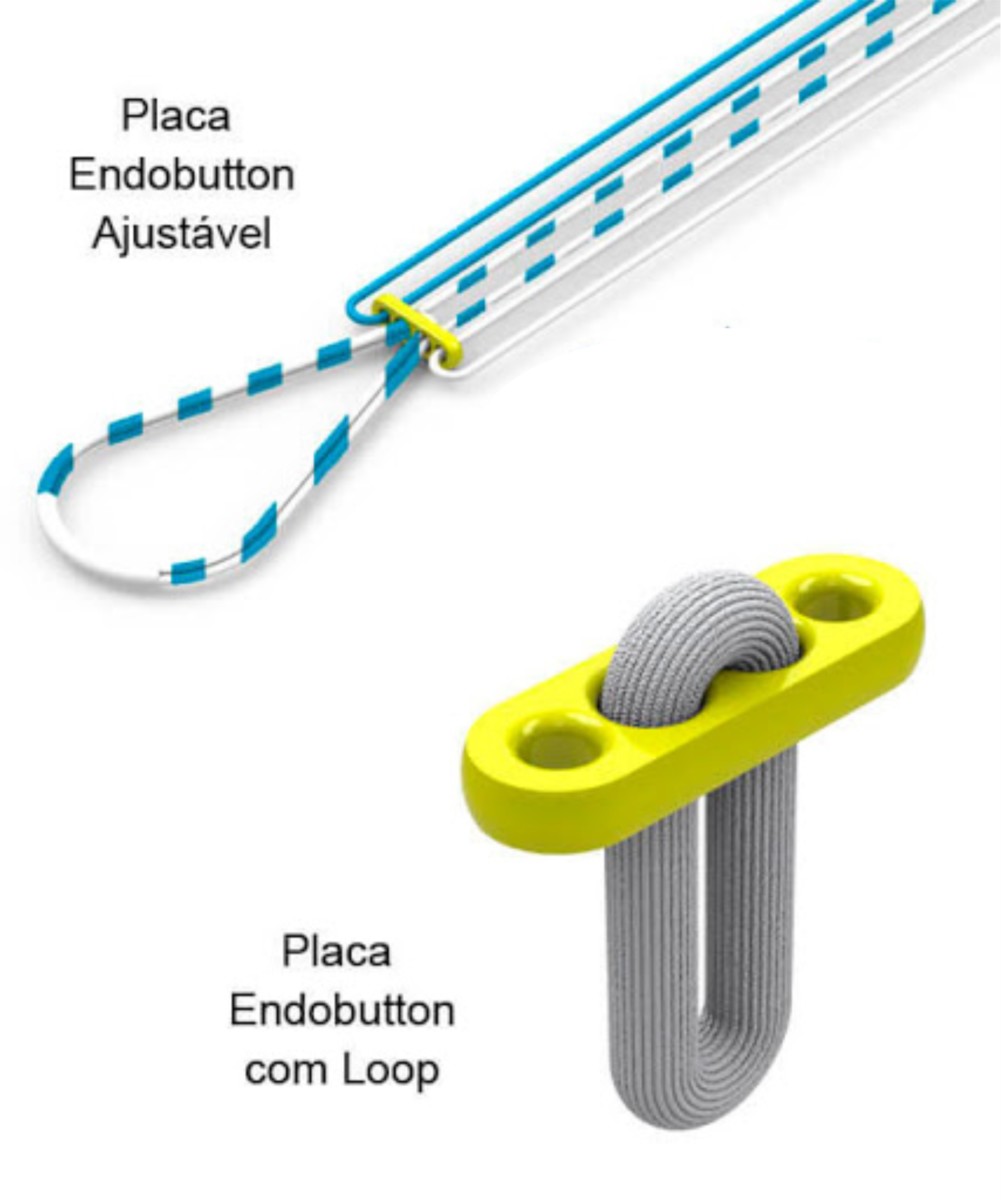

Placa Endobutton Ajustável

A Placa de Reconstrução Ligamentar é um dispositivo implantável, não ativo, invasivo cirurgicamente e de uso único. Desenvolvida para garantir a reconstrução do ligamento cruzado anterior e posterior.

A Placa de Reconstrução Ligamentar é composta de:

- Placa de titânio.

- Fio de Sutura UHMW PE USP – Ø 0,5 mm

Sistema de Reconstrução se caracteriza como um dispositivo de reconstrução ligamentar de tamanho único. Sua principal aplicação ocorre em lesões do ligamento cruzado (LCA / LCP).

Seu projeto inovador permite o ajuste da sutura pelo cirurgião, o que garante maior precisão no balanceamento ligamentar sem que haja a necessidade de realizar os cálculos para determinar o tamanho da laçada e profundidade.

Após o ajuste, não é necessário executar a amarração da sutura na placa. Essas características especiais reduzem o tempo cirúrgico e contribui para uma recuperação mais rápida e com menos risco ao paciente.